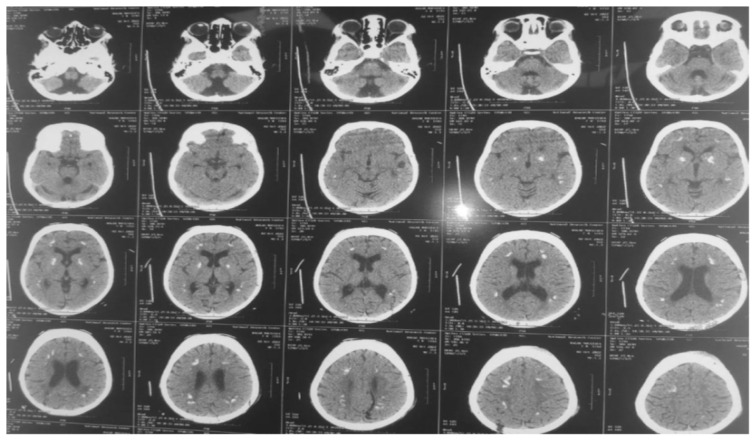

叶酸受体 1 基因(FOLR1)突变导致的脑叶酸转运缺陷,是由于叶酸通过血液:脉络膜:脑脊液(CSF)屏障的转运功能受损所致。这导致脑脊液中活性叶酸代谢物 5-甲基四氢叶酸含量偏低。我们报告了两名患有这种可治疗的脑叶酸转运缺乏症的儿童。八岁零九个月大的女婴发育迟缓,随后出现退步、癫痫发作和意向性震颤。经检查,患儿有小头畸形、全身肌张力低下、反射亢进、步态不稳和不协调等症状。脑部磁共振成像(MRI)显示脑室系统扩张和小脑萎缩。脑部计算机断层扫描(CT)显示脑部钙化。最后进行了全外显子测序,发现FOLR1基因第3外显子c.C382T p.R128W存在同型无义致病变异,确诊为脑叶酸缺乏症。12岁的女患儿自出生后就出现全面发育迟缓、肌阵挛性抽搐和认知能力退化。患儿全身肌张力低下,反射亢进。她的协调能力明显受到影响,并伴有意向性震颤和步态不平衡。脑部 CT 显示双侧基底节和脑室周围钙化,并伴有脑萎缩病变。脑部核磁共振成像显示小脑叶突出,伴有轻度脑萎缩病变。基因检测显示,在 FOLR1 C.327_328 delinsAC, p.Cys109Ter 中发现了一个同卵致病变体。两名患者开始肌肉注射亚叶酸,癫痫发作频率有所下降。然而,由于开始治疗较晚,他们的癫痫发作并没有完全停止。总之,如果患儿出现全面发育迟缓、顽固性肌阵挛性癫痫、共济失调并伴有神经影像学提示的小脑萎缩和脑钙化,则应怀疑其脑叶酸转运缺乏症。如果诊断较晚且治疗启动延迟,则对补充亚叶酸的反应是部分的。

Cerebral folate transport deficiency due to folate receptor 1 gene (FOLR1) gene mutation results from impaired folate transport across the blood: choroidplexus: cerebrospinal fluid (CSF) barrier. This leads to low CSF 5-methyltetrahydrofolate, the active folate metabolite. We are reporting two children with this treatable cerebral folate transport deficiency. Eight years and 9-month-old female presented with delayed milestones followed by regression, seizures, and intention tremors. On examination child had microcephaly, generalized hypotonia, hyperreflexia, unsteady gait, and incoordination. Magnetic resonance imaging (MRI) of brain revealed dilated ventricular system and cerebellar atrophy. Computed tomography (CT) of brain showed brain calcifications. Whole exome sequencing was finally performed, revealing homozygous nonsense pathogenic variant in FOLR1 gene in exon 3 c.C382T p.R128W, confirming the diagnosis of cerebral folate deficiency. Twelve-year-old female child presented with global developmental delay since birth, myoclonic jerks and cognitive regression. Child had generalized hypotonia and hyperreflexia. Her coordination was markedly affected with intention tremors andunbalanced gait. CT brain showed bilateral basal ganglia and periventricular calcifications with brain atrophic changes. MRI brain showed a prominent cerebellar folia with mild brain atrophic changes. Genetic testing showed a homozygous pathogenic variant was identified in FOLR1 C.327_328 delinsAC, p.Cys109Ter. Both patients were started on intramuscular folinic acid injections with a decrease in seizure frequency. However, their seizures did not stop completely due to late initiation of therapy. In conclusion, cerebral folate transport deficiency should be suspected in every child with global developmental delay, intractable myoclonic epilepsy, ataxia with neuroimaging suggesting cerebellar atrophy and brain calcifications. Response to folinic acid supplementation is partial if diagnosed late and treatment initiation is delayed.